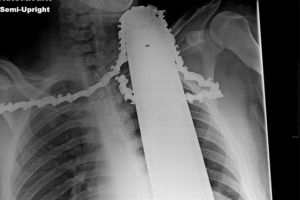

가슴에서 목까지 전기톱 박힌 남성, 기적적으로 생존